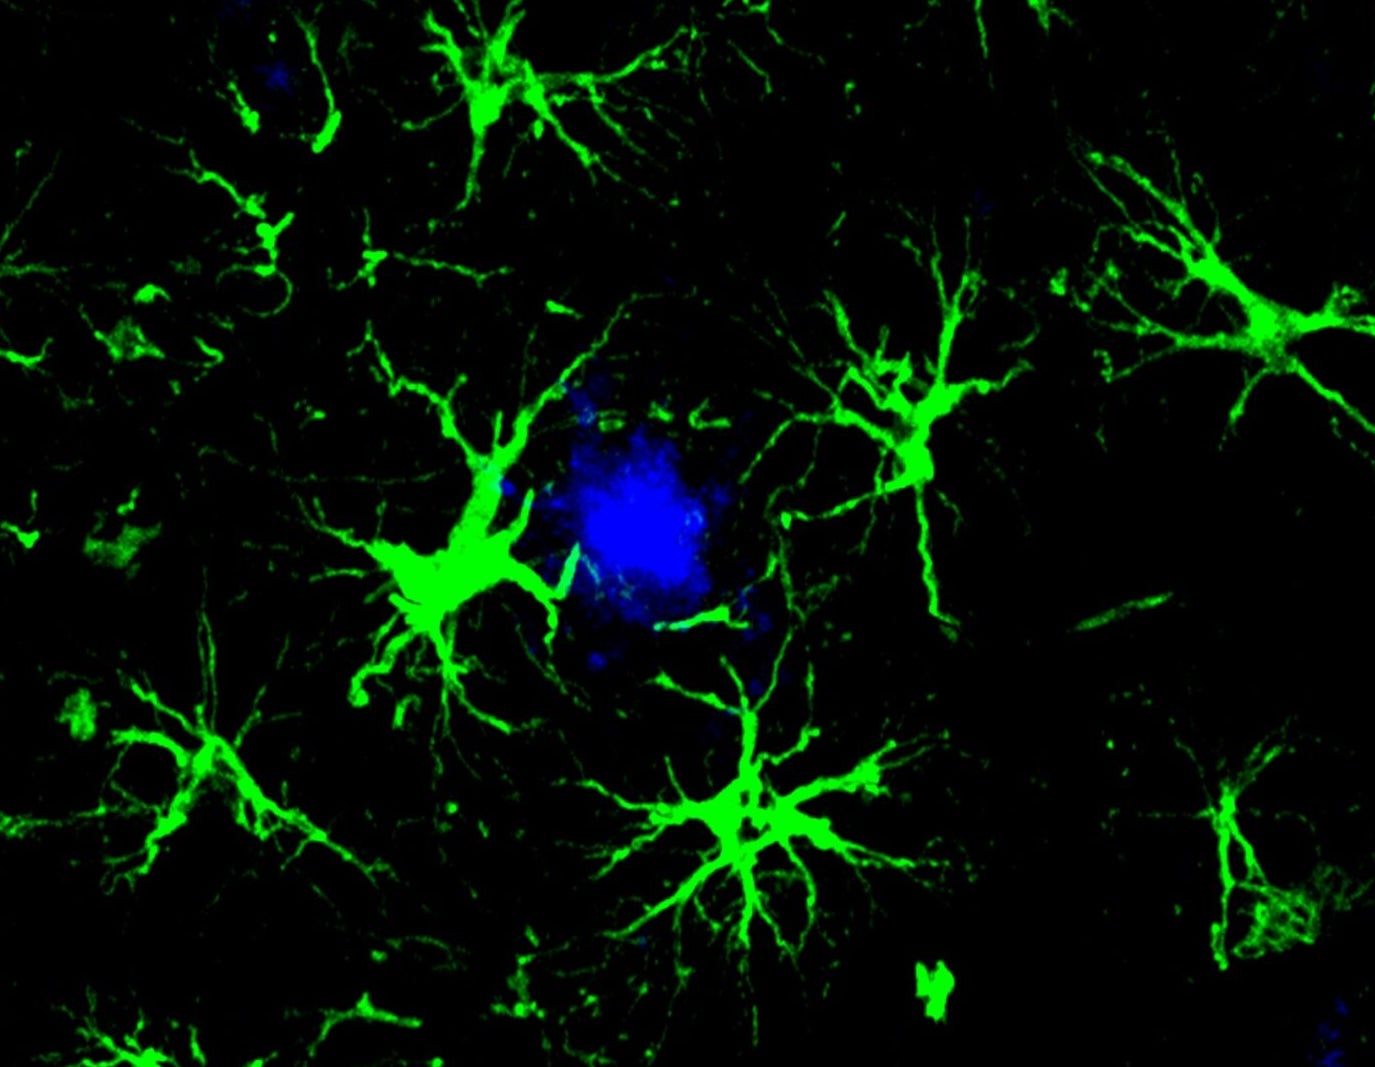

Taking a page from CAR T, a team at the Washington University School of Medicine, St. Louis has now transformed brain cells, known as astrocytes, into amyloid-gobbling machines.

A single injection into mice with Alzheimer’s prevented the formation of amyloid clumps in the brain during the disease’s early stages. In mice whose brains were already riddled with the toxic plaques, the treatment cut amyloid levels roughly in half.

“This study marks the first successful attempt at engineering astrocytes to specifically target and remove amyloid beta plaques in the brains of mice with Alzheimer’s disease,” study author Marco Colonna said in a press release.

Inside the brain, the treatment transformed naturally occurring astrocytes into CAR-A cells. In mice two and a half months old, roughly late adolescence in human years, the cells prevented amyloid clumps for at least three months. And a single shot slashed amyloid levels in half for older mice already suffering buildup. The treatment also protected neurons from further damage.

Though tailored to astrocytes, the gene therapy also caused the brain’s immune cells to more readily devour amyloid plaques, swept away malfunctioning ones, and lowered inflammation. Shifting some of the amyloid-clearing burden from immune cells to astrocytes could create a less toxic environment in the Alzheimer’s brain, wrote Boles and Gate.